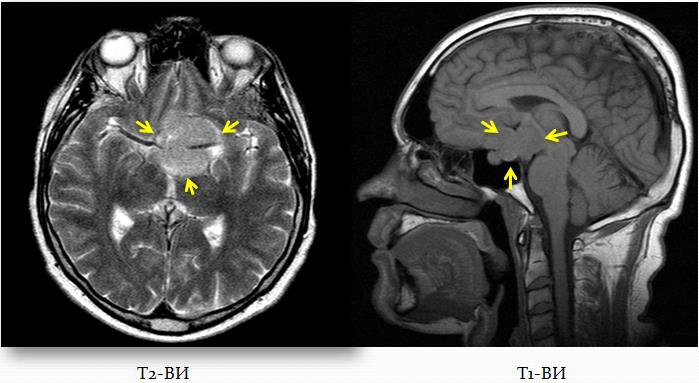

Глиоз что это и как лечить 111 фотографий